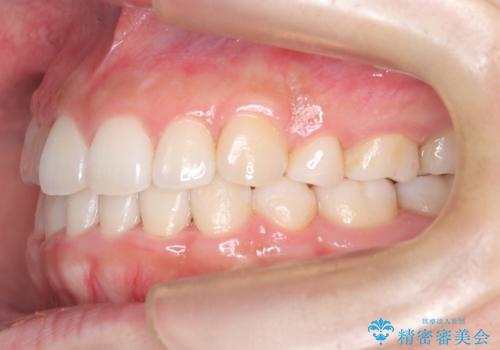

八重歯を改善!美しい口元を実現するハーフリンガル矯正

- 矯正装置

- ハーフリンガル

- 前歯のガタツキと口元のコンプレックスを解消するために来院されました。

ハーフリンガルワイヤー矯正で治療を開始しました。

ハーフリンガル矯正は、見た目を気にせずに矯正治療ができる方法です。この治療法は、八重歯や前歯のガタツキを効果的に改善します。特徴として、ワイヤーが上の歯の裏側に装着されるため、装置が外から見えません。これにより、治療中も自然な笑顔を保ちながら安心して治療を続けることができます。歯並びの悩みを持つ方にとって、非常に魅力的な選択肢です。